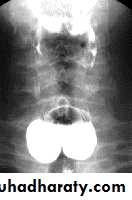

Hypertrophic pyloric stenosisCause:A. Congenital typeB. Adult type

Epidemiology:-

Pyloric stenosis is relatively common and has a male predilection (M:F ~ 4:1), and is more commonly seen in Caucasians 4.

It typically occurs between the 4-8 weeks of life. There may be a positive family history.

Incidence of hypertrophic pyloric stenosis is approximately 2-5 per 1,000 births per year in most white populations.

In a normal situation, the pyloric muscle thickness (diameter of a single muscular wall on a transverse image) should normally be less than 3 mm (most accurate 3) and the length (longitudinal measurement) should not exceed 15 mm.